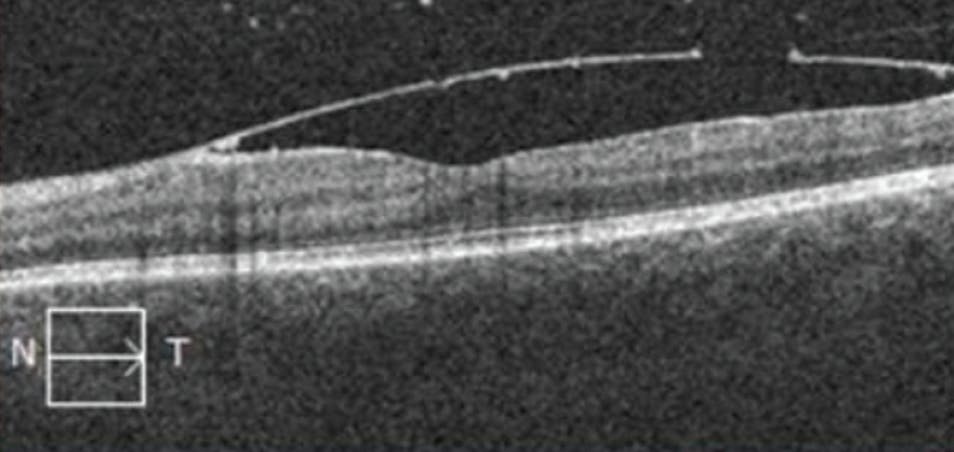

After discussion with the patient, she was treated with Nd:YAG laser of the posterior hyaloid/ILM to release the hemorrhage (Figure 2). After treatment, a break in the ILM can be seen on OCT (Figure 3). At the 1-week follow-up, the patient’s VA improved to 20/40, with further improvement to 20/30 upon resolution of mild inferior vitreous hemorrhage.

<p>Figure 3. OCT of the left eye after Nd:YAG laser reveals a small break in the ILM.</p>

Figure 3. OCT of the left eye after Nd:YAG laser reveals a small break in the ILM.